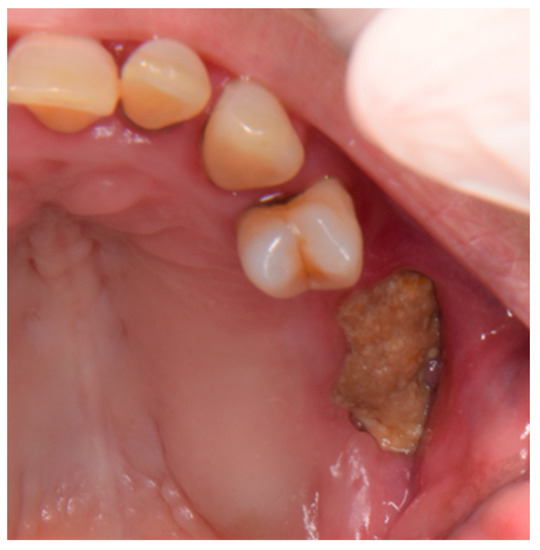

2. Case Report